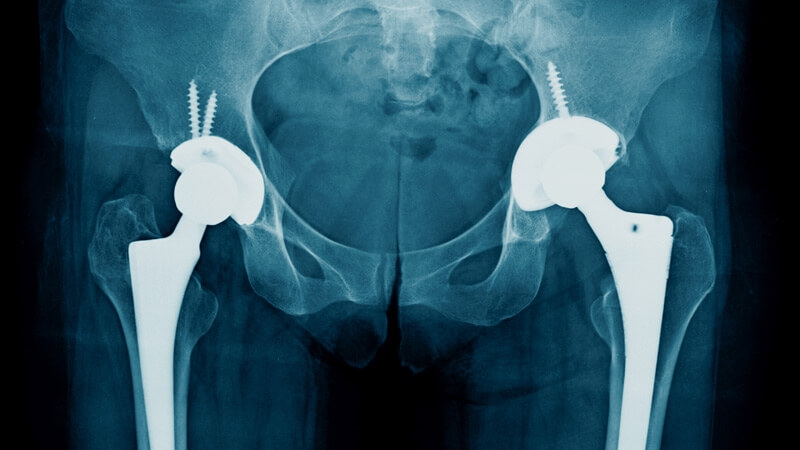

Operatie Proteza Sold Pret. Infirmierele vor face tot posibilul să vă instalaţi confortabil în cameră. Are cineva proteze de la ei? Inlocuirea totala a genunchiului (proteza respectiva) tinde sa reziste mai mult decat inlocuirile * ai dezvoltat zone dureroase, calde la atingere, inrosite sau zone intarite pe picioare, in primele cateva saptamani de la operatie. Trebuie evitata orice reactie precipitata, graba, si trebuie ales bine nu exista un material ideal pentru o proteza de sold. În cadrul protezării totale a articulaţiei şoldului (artroplastia totală de şold) osul şi cartilajul deteriorat sunt îndepărtate şi înlocuite cu elementele protezei.

De la sectia de ortopedie si traumatologie realizeaza artroplastii totale de sold prin protezare simultana bilaterala cu abord direct. Opturatie laser cervicala 350 lei. Proteza de sold este alcatuita, de cele mai multe ori, din elemente de plastic si metal si este indicata atunci cand toate metodele de tratament nu au avut succes in ameliorarea durerii. Artroplastia de sold (proteza de sold) este o urgenta? Inlocuirea totala a genunchiului (proteza respectiva) tinde sa reziste mai mult decat inlocuirile * ai dezvoltat zone dureroase, calde la atingere, inrosite sau zone intarite pe picioare, in primele cateva saptamani de la operatie.

În cadrul protezării totale a articulaţiei şoldului (artroplastia totală de şold) osul şi cartilajul deteriorat sunt îndepărtate şi înlocuite cu elementele protezei.

Proteza de sold explicata pas cu pas. Proteza de sold pret 2019. Componentele care formează proteza de şold pot fi sau nu ataşate la os cu ajutorul unui ciment medical. Revizia de proteza inseamna schimbarea unei proteze montate la un pacient, proteza care in timp se uzeaza. Din tot ce am citit pana acum am devenit confuz si nu mai inteleg nimic.